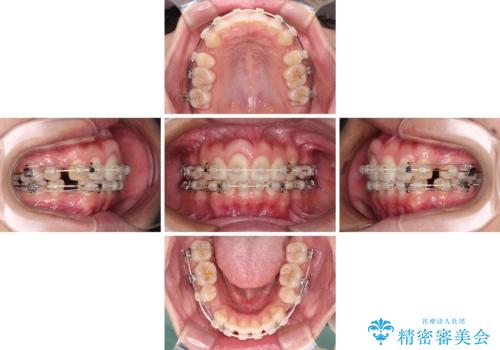

- 矯正装置

- 審美装置

- 前歯の出っ歯と口元の閉じにくさを気にして来院された患者様です。

口元を積極的に引っ込めるために、上下左右の小臼歯4本を抜歯することとしました。

4本の歯を抜歯したことで、飛び出していた口元が引っ込み、横顔が大きく改善されました。

咬み合わせが悪化することのないようにスペースを閉じていくことができ、比較的スムーズに治療を進めることができました。